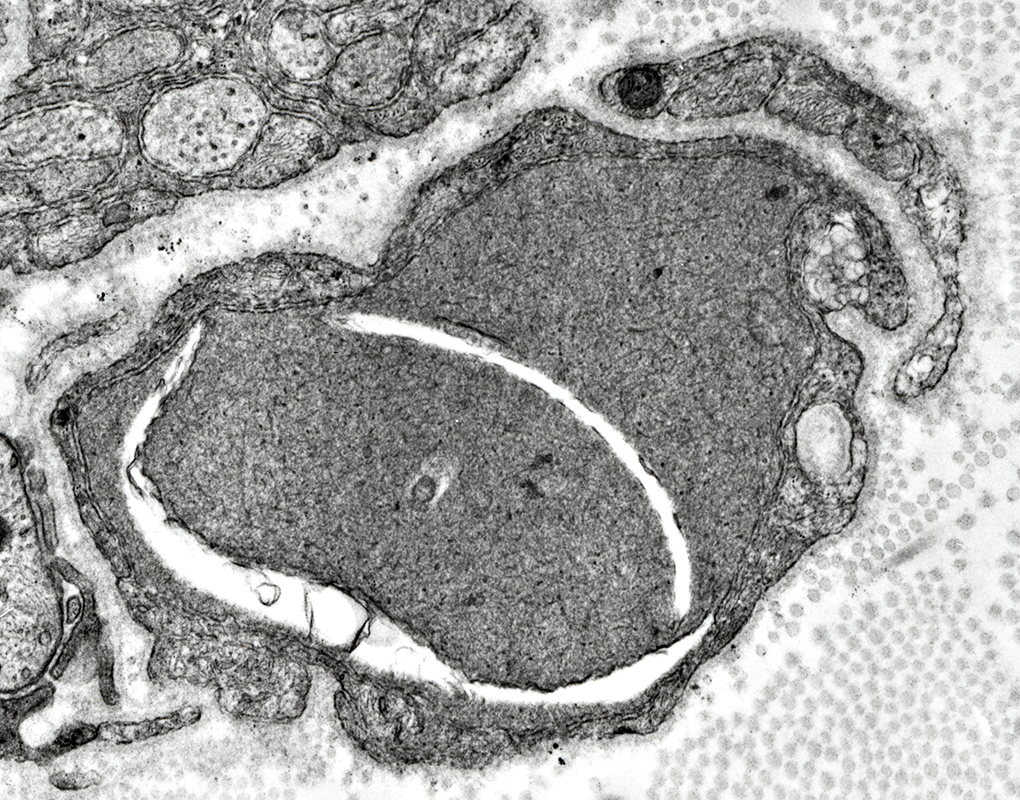

Early phase: Autophagic Schwann cell

Myelin, compact: Fragmentation inside Schwann Cell

Schwann cell characteristic: Surrounded by Basal lamina (Below; Arrow)

Axon is lost

Autophagic Schwann cell

Contains: Myelin fragments & Lipid droplets

Robert E Schmidt MD